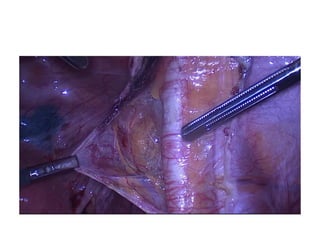

Cervical

Sen$nel

LN

mapping

•  the

stroma

is

injected

circumferen$ally.

Peri-­‐

tumoral

injec$on

preferred,

as

it

should

allow

the

tracer

to

follow

same

path

lympha$c

drainage

of

lesion

itself.

Near-­‐infrared

fluorescence

imaging

using

indocyanine

green